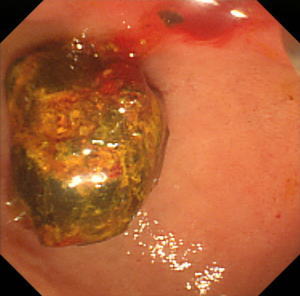

乳頭拡張後に採石用のバスケット(金属線の器具)を用いて結石を破砕することなく除去しました。 |

除去した結石です。この方法では結石を破砕しなくて済むため、1回の処置でほぼすべての結石を除去することができます。 |